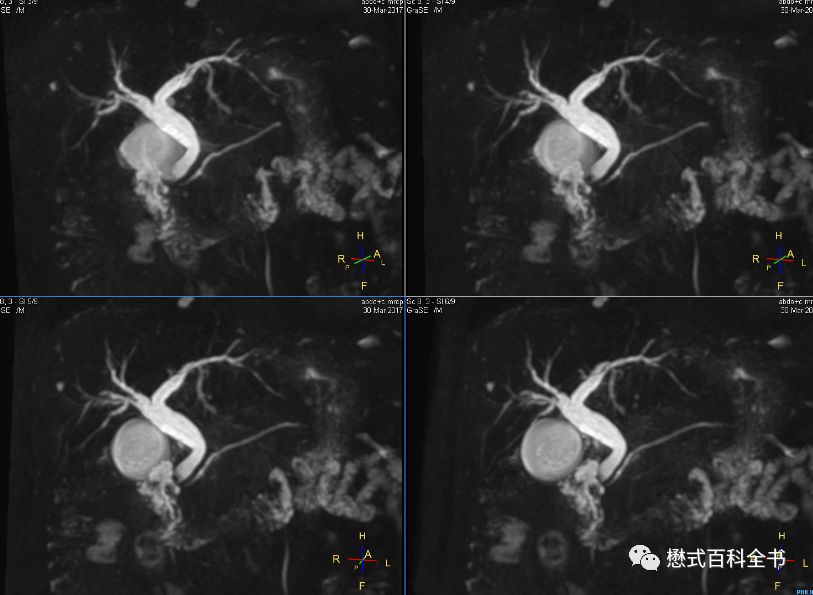

图19:MRCP扫描角度二

如上图所示,第二种扫描角度,是在3D冠状位扫描的时候,在横轴位上,扫描角度平行于左、右肝内胆管走形。使用该定位角度显示左、右肝内胆管及肝总管比较好,而且大家关注,使用这种角度,配合合适的FOV和扫描层数可以躲避到腹主动脉。而使用第一种定位角度,一般是无法躲避腹主动脉的。